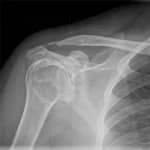

X Ray Scan in Dubai: Fast Bone & Chest Imaging

Digital technology for fractures, chest conditions, and joint assessment

Bone Fractures

Detection of broken bones in any part of the body, including hairline fractures, displaced fractures, and stress fractures common in athletes and active individuals.

Wear comfortable, loose-fitting clothing without metal components such as zippers, buttons, snaps, or underwire. For a chest X-ray, a plain cotton t-shirt without prints or embellishments is ideal. For limb X-rays, wear clothing that allows easy access to the area being scanned, such as shorts for a knee X-ray or a short-sleeved top for a shoulder X-ray. You will be asked to remove all jewelry, watches, piercings, and hair accessories from the scan area. In some cases, you may need to change into a hospital gown to ensure the highest image quality.